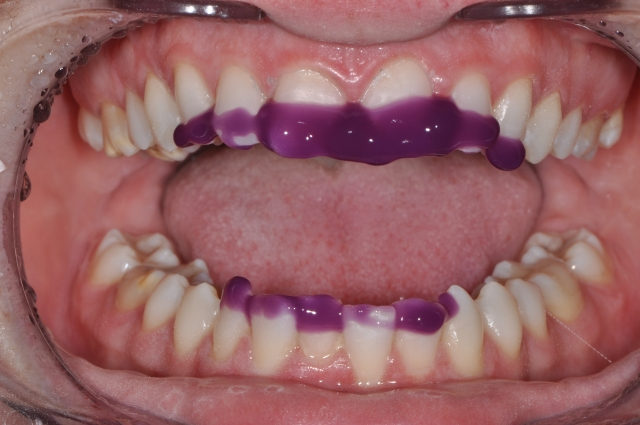

- Microetch the tooth surface affected, then rinse with water.

- Apply 37% phosphoric acid on the affected tooth surface for 2 minutes, followed by rinsing the site with water.